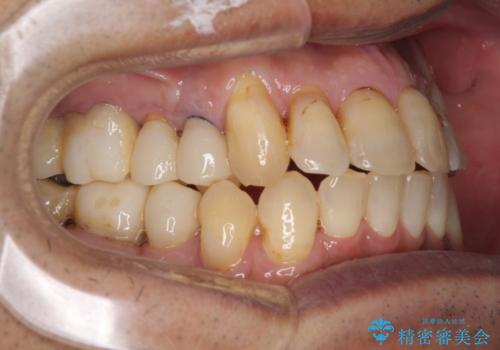

- 前歯がのデコボコや、奥歯に咬んだときに痛みがあるとのことで来院された患者様です。

全体的に問題が多く、全てをしっかりと治療したいとのことでした。

全体的に中等度の歯周病と診断されたため、歯周外科処置やインプラントによる咬合回復から進めて行き、矯正治療による歯列改善を行った後にオールセラミッククラウンにて補綴することとしました。

歯槽骨の再生治療を行ったため、外科処置後の静置期間がながくなり、4年弱の治療期間となりました。